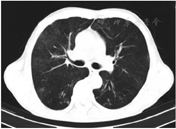

住院期间患者治疗极不配合、烦躁、拒绝交流,症状逐渐加重,入院后第15天心理科会诊加用奥氮平2.5 g夜间鼻饲、草酸艾司西酞普兰片10 mg 1次/d鼻饲,服药2 d后症状好转,同时P/F上升至253 mmHg,气道分泌物减少,逐步间断撤离呼吸机。入院后第17天复查CT示两肺多发炎症,较前吸收,右肺下叶炎性小结节,双侧胸膜增厚(图3)。患者入院后第19天,呼吸机撤离24 h后动脉血气分析:pH 7.48,PaO2 199 mmHg,PaCO2 36.1 mmHg,P/F 485 mmHg,予更换金属气管导管,后患者经口进流质呛咳,喉镜检查咽喉部未见明显异常。入院后第24天拔除金属气管导管。患者病情平稳,办理出院回当地医院治疗。出院诊断:戊二醛中毒、吸入性肺炎、肺部感染。出院后当地医院继续予抗感染、化痰等对症支持治疗。发病1个月后随访,患者未诉不适,已停用奥氮平和草酸艾司西酞普兰片;8月5日复查胸部CT示两肺渗出基本吸收(图4),3个月后随访未出现吞咽困难、呼吸困难等症状,未留有后遗症。

两肺渗出进一步吸收,右肺下叶炎性小结节可能

右肺下叶小结节